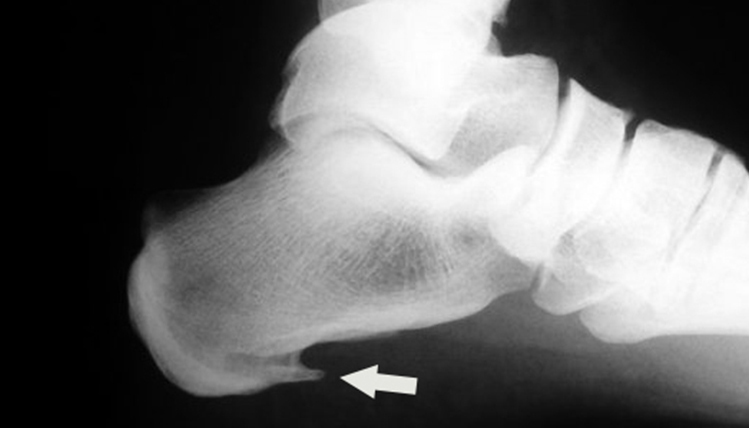

En ocasiones se confunde la fascitis plantar con el espolón calcáneo. Podemos hablar de espolón cuando observamos una calcificación del tubérculo postero-medial del calcáneo en las pruebas radiológicas.

En esta radiografía se observa un “saliente puntiagudo” desde el talón hacia el interior del pie, indicando la patología de espolón calcáneo. Si en las pruebas no aparece dicha calcificación, se trata entonces de fascitis plantar.

Los síntomas y el tratamiento van a ser muy parecidos en ambos casos. El espolón aparece por mantener una tracción continuada de la fascia contra el calcáneo. Esa tensión aparece en la fase inicial la fascitis plantar, y si se mantiene en el tiempo, posiblemente generará el espolón calcáneo. El objetivo del tratamiento es “destensar” la fascia para que disminuya la inflamación y el dolor.